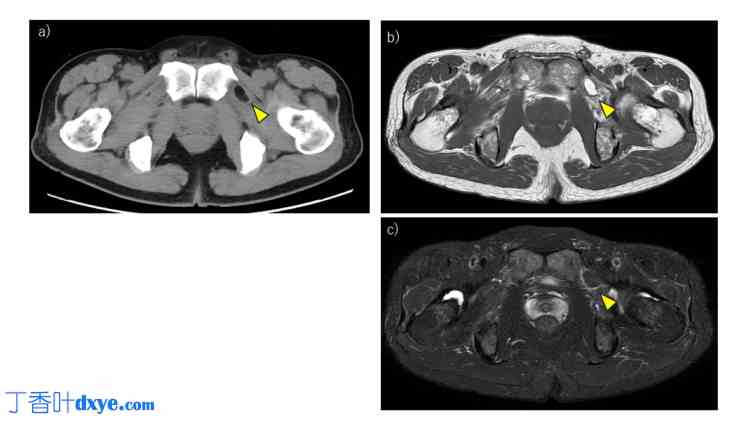

腹部CT显示脂肪组织疝入左侧闭孔管(图1a)。MRI显示T2加权像高信号(图1b)和脂肪抑制像信号抑制(图1c),证实病变为脂肪组织,未累及肠道。这些影像学表现提示疝出的脂肪组织压迫闭孔神经。根据临床症状和影像学表现,诊断为闭孔疝,尽管患者年龄和性别不典型,但仍建议行手术修补。

图1. 术前影像。

(a) CT 显示脂肪疝入左侧闭孔管(黄色箭头)。(b) MRI T2 加权像显示相应区域高信号强度(黄色箭头)。(c) 脂肪抑制 MRI 显示同一病灶信号抑制(黄色箭头)。